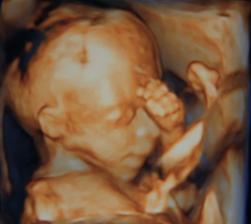

14.12.2010 dnes sme boli na morfologickom utz. ,všetko je v poriadku,len malinké sa akosi hambí,ešte aj nožičky prekrížilo. Pán dr. musel do neho štuchať lebo ani za nič na svete sa nechcelo otočiť a ukazoval nám ritku :°) Štuchal mi do bruška a malé sa len pomrvilo a to bolo všetko. Dr. povedal,že už od malička taký tvrdohlavý. A ručičky pred tváričku sa nás hambil. Aj 3D foto nám pán dr. dal :°) 20+2tt